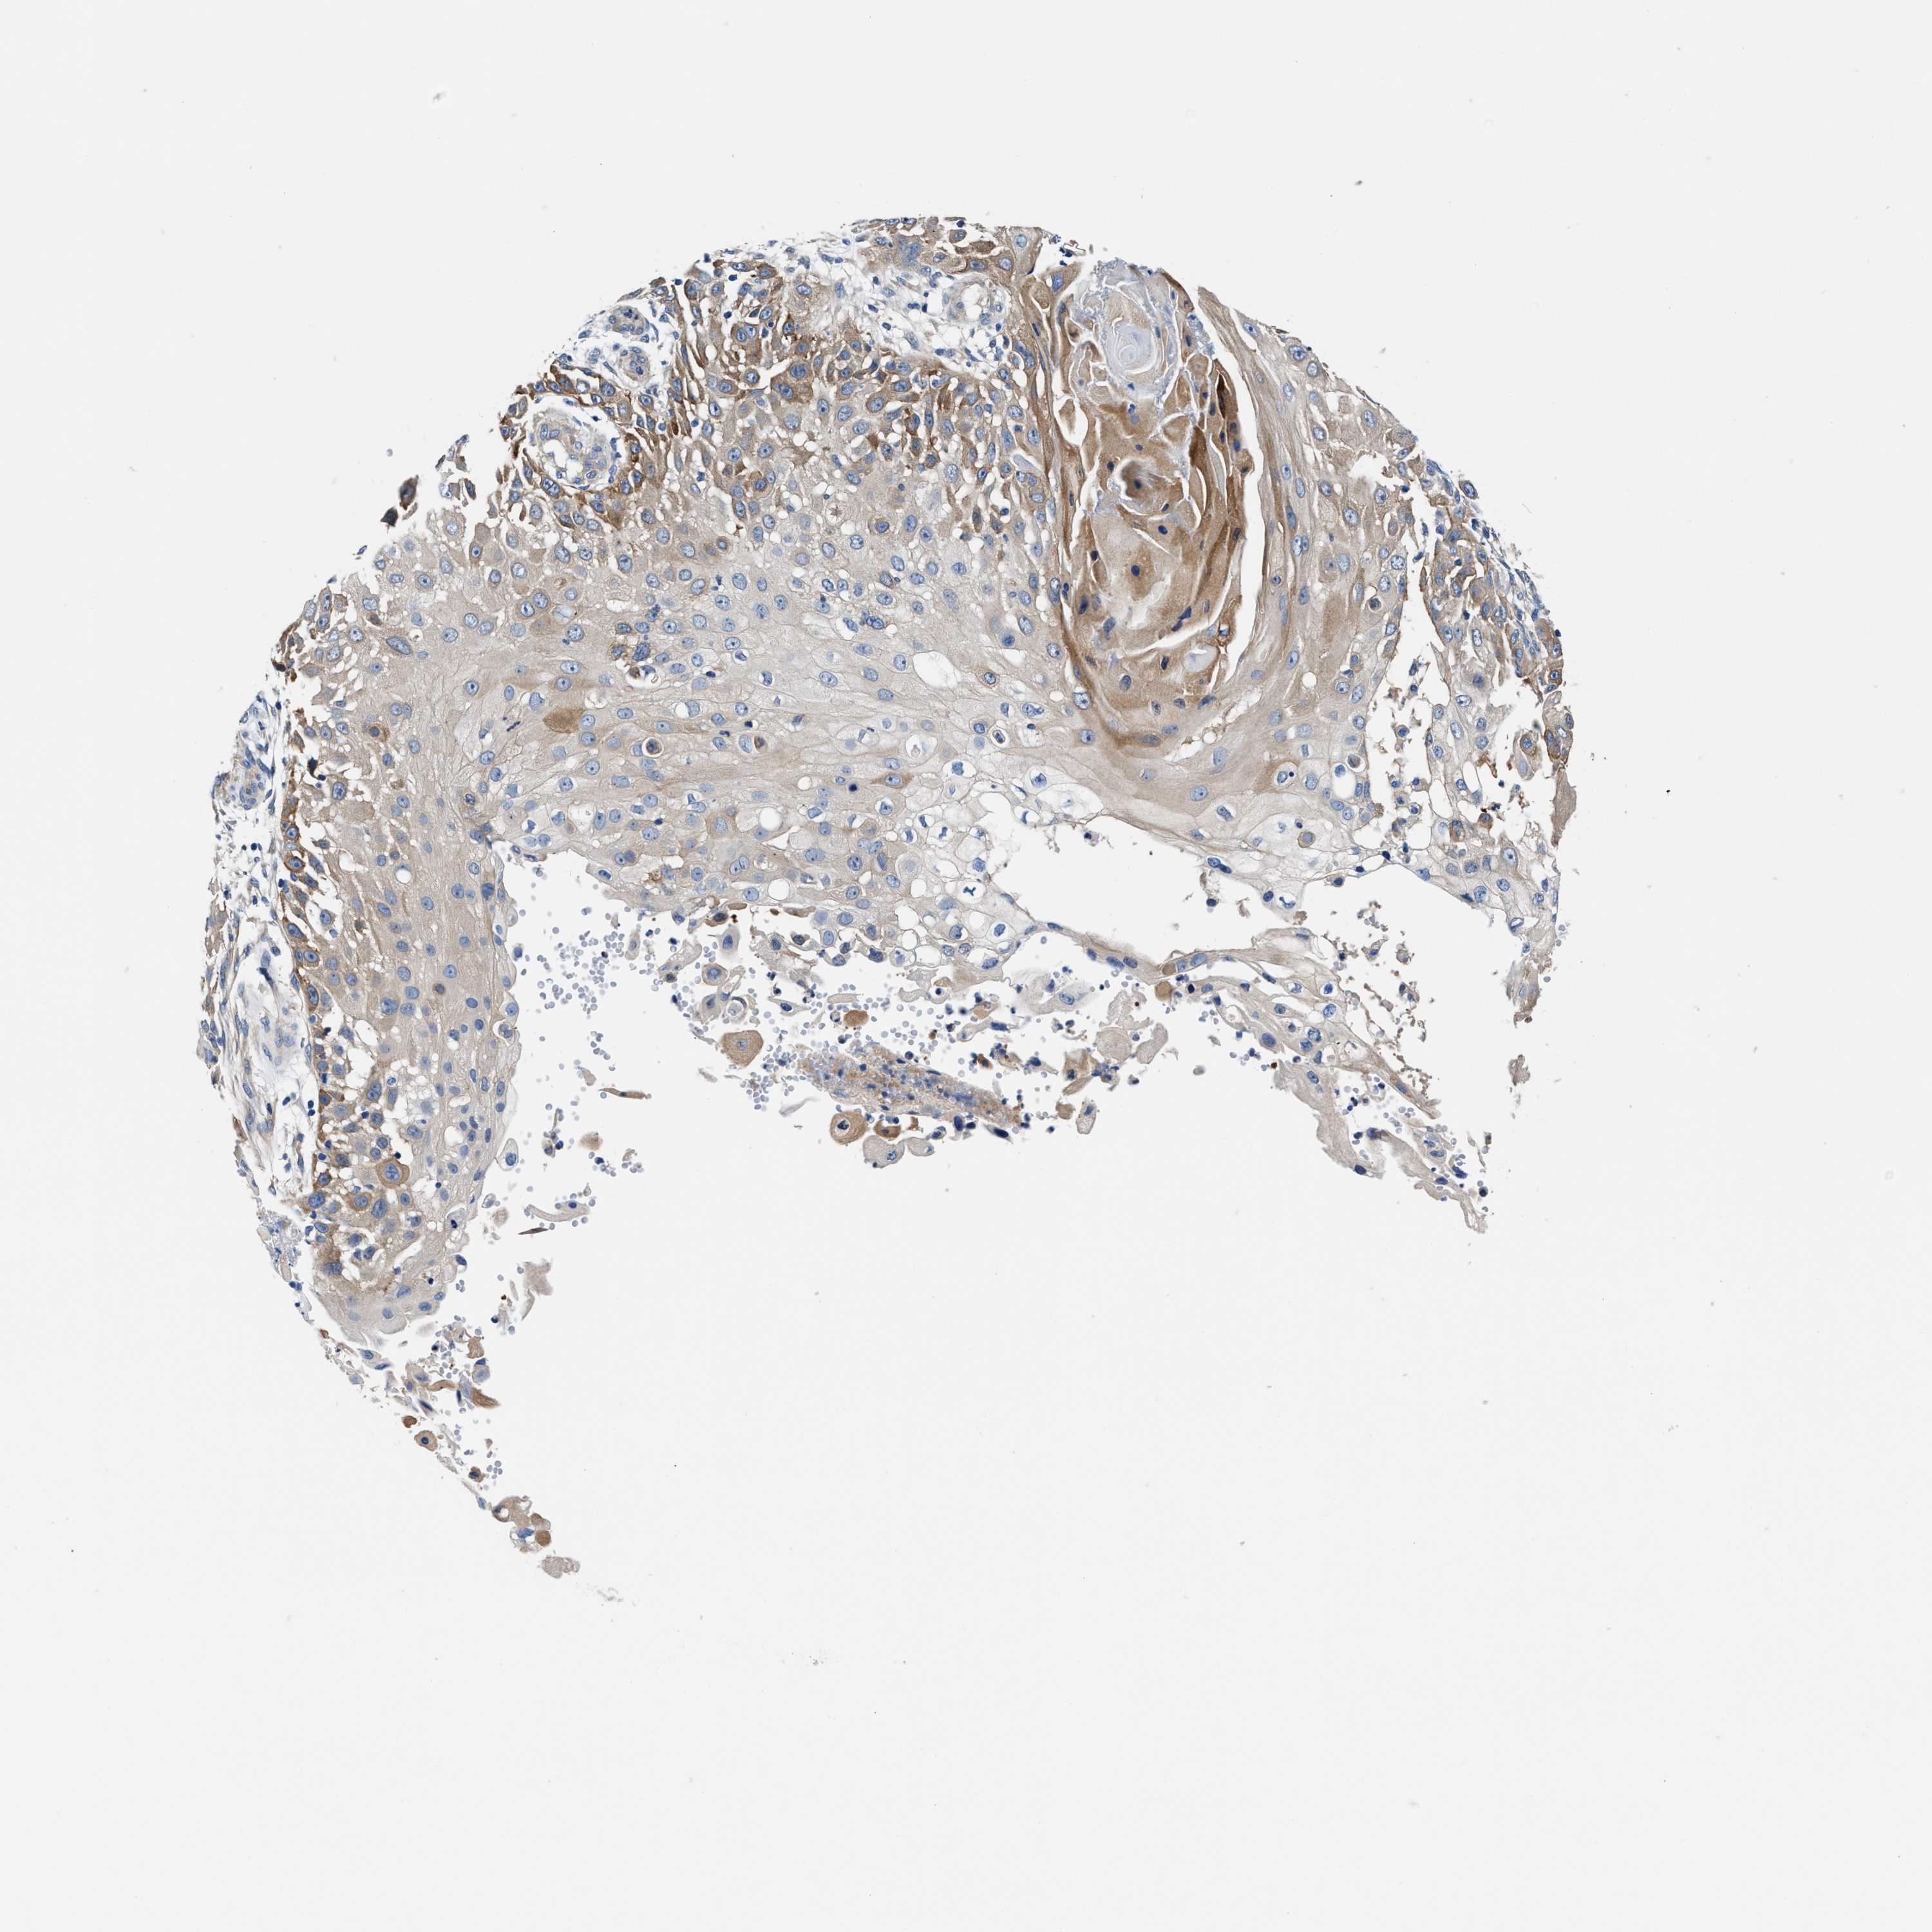

Basal cell and squamous cell cancer

SKIN CANCER - Protein expressioni

A mouse-over function shows sample information and annotation data. Click on an image to view it in a full screen mode. Samples can be filtered based on level of antibody staining by selecting one or several of the following categories: high, medium, low and not detected. The assay and annotation is described here.

Antibody stainingi

Antibody staining in the annotated cell types in the current human tissue is reported as not detected, low, medium, or high, based on conventional immunohistochemistry profiling in selected tissues. This score is based on the combination of the staining intensity and fraction of stained cells.

Each image is clickable and will lead to virtual microscopy that enables deeper exploration of all samples and also displays staining intensity scores, fraction scores and subcellular localization as well as patient and tissue information for each sample.

Antibody HPA021819

Staining

High

Medium

Low

Not detected

Intensity

Strong

Moderate

Weak

Negative

Quantity

>75%

75%-25%

<25%

None

Location

Nuclear

Cytoplasmic/membranous

Cytoplasmic/membranous,nuclear

Basal cell carcinoma